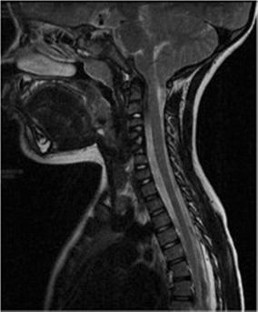

The authors describe three cases of congenital scoliosis in monozygotic twins. The first pair includes two 4-year-old girls presenting with mirror curves, one of whom had an associated stage I Chiari malformation. The second pair is a 4-year-old girl who presented with thoracic scoliosis, a T10–11 hemivertebra, and multilevel failure of segmentation in the lumbar spine whose identical sibling is unaffected. The third pair includes a 4-month-old boy with T9 and L4 hemivertebra whose brother is also unaffected.

All three cases were managed conservatively with observation and remained asymptomatic throughout the duration of follow-up. There were no associations with extraspinal deformities, although one patient presented with concomitant type I Chiari malformation.